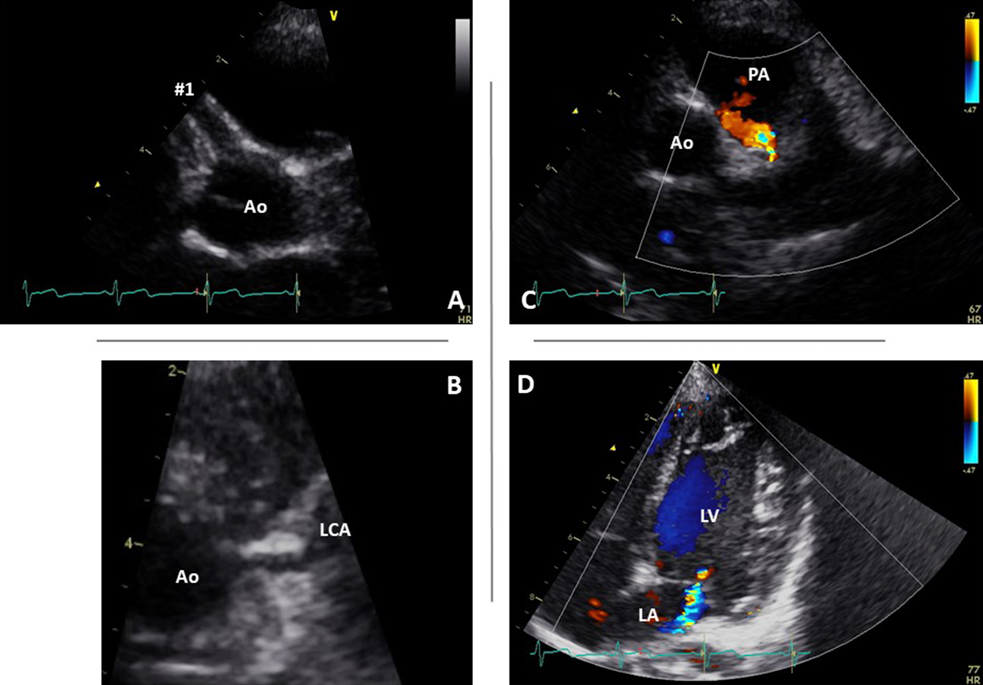

Chest radiograph showed normal cardiothoracic ratio of 49% and there was no lung congestion. A resting 12-lead electrocardiogram showed normal sinus rhythm at 97 beats per minute, mild left axis deviation, normal PQ interval, and negative T wave in aVL. However, there were no abnormal Q waves in any lead and no arrhythmias present. Echocardiography (Fig. 2) showed normal left ventricular end-diastolic dimension [35.1 mm (+0.6 SD)] with normal ejection fraction of 75% without asynergy and mild mitral regurgitation without apparent prolapse. The right coronary artery was further dilated [segment 1, 4.6 mm (+6.7 SD); segment 2, 3.3 mm; and segment 3, 1.6 mm]; however, the left coronary artery was within normal range [segment 5, 2.3 mm (+0.2 SD)]. Although the origin of the left coronary artery appeared normal on B-mode echocardiography (Fig. 2B), the normal forward flow of the coronary artery was not documented.

Journal of Pediatric Cardiology and Cardiac Surgery 7(1): 36-40 (2023)

Fig. 2 Echocardiographic findings of the patient during the first visit to our institution

(A) Parasternal short axis of the aortic root shows right coronary artery dilation of 4.6 mm at #1. (B) In this view, the left coronary artery appears to be normally connected with the aorta. (C) Color Doppler echocardiography of tilted parasternal short axis view shows abnormal flow into the main pulmonary artery. (D) Color Doppler echocardiography at the apical four-chamber view shows mild mitral regurgitation. Ao, aorta; LA, left atrium; LCA, left coronary artery; LV, left ventricle; PA, pulmonary artery.

In this report, we present the case of a 6-year-old child with ALCAPA who had been diagnosed and managed at a previous local hospital as a case of right coronary artery enlargement associated with acute stages of KD. When coronary artery enlargement is detected by echocardiography in the early stage of KD, congenital coronary artery anomalies should be included in the differential diagnosis. One of the factors for the misdiagnosis of enlarged coronary arteries due to KD was that the left coronary artery appeared to have a normal origin from the aorta on echocardiography. In fact, it is not uncommon in ALCAPA for the left coronary artery to appear to originate normally from the aorta on echocardiography. Therefore, to differentiate ALCAPA, not only should the continuity between the aorta and the left coronary artery be observed in B-mode, but also the direction of blood flow in the left coronary artery and the presence or absence of blood flow into the pulmonary artery should be confirmed by color Doppler.6, 7) If the origin of the coronary artery is not clear, looking at the left ventricular myocardium with low-speed color Doppler will reveal abnormal signals from many collateral blood vessels draining from the right coronary artery to the left coronary artery, leading to a suspicion of ALCAPA-related disease.8) In this case, the coronary artery appeared to originate from the left coronary cusp, but we were able to confirm the retrograde blood flow into the pulmonary artery. In addition, many abnormal collateral signals from the right coronary artery were observed in the retrospective echocardiographic review.